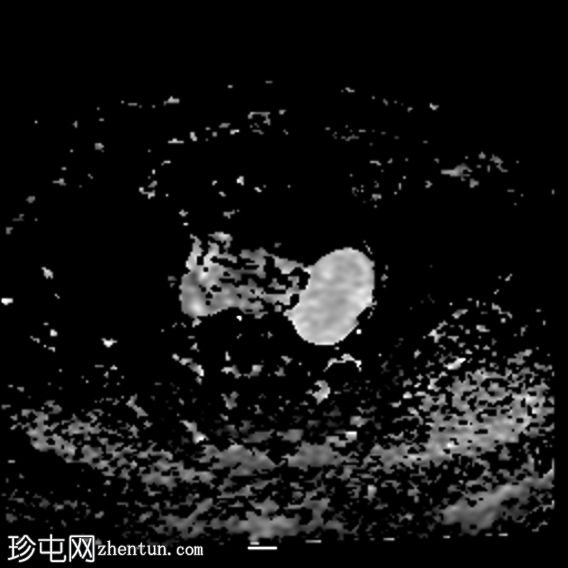

轴位

ADC

左侧卵巢增大,呈弥漫性低T1信号和高T2信号,可见周边卵泡,部分卵泡除周边卵泡周围有环状强化外,无明显实质强化。左侧附件蒂呈漩涡状,提示卵巢扭转。